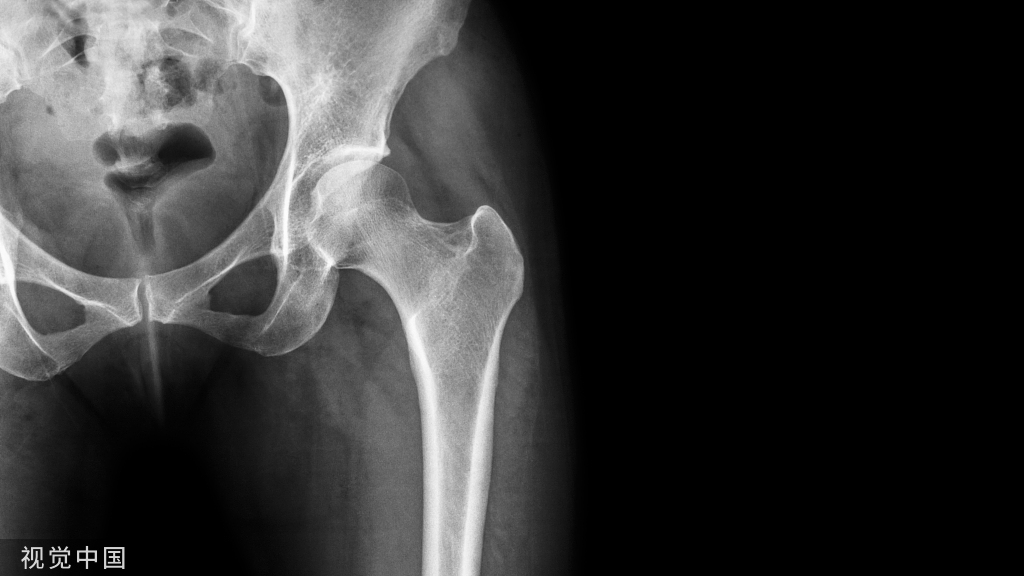

影像学检查方法

X线检查基本特征1.关节间隙变窄:成人膝关节间隙为4mm,小于3mm即为关节间隙狭窄,60岁以上的老人膝关节间隙为3mm,小于2mm为关节间隙狭窄。2.软骨下骨板硬化:软骨下骨板致密、硬化,负重软骨下骨质内可见囊性改变。3.骨赘形成

关节软骨的改变:软骨水肿、软骨囊性变、软骨变薄、磨损、软骨破坏